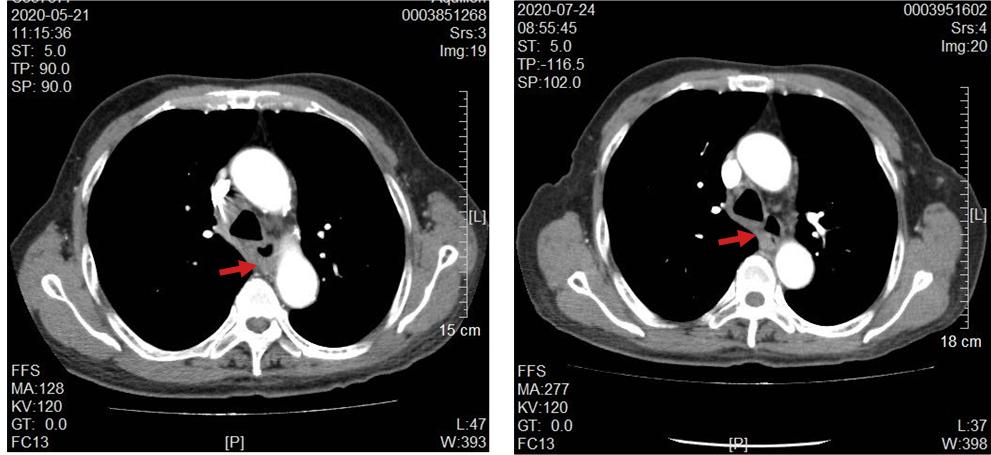

林老师在2月个半月因吞咽困难,进食固体食物时明显,半流质尚可,后进行性加重伴右侧颈部淋巴结肿大,淋巴结自行触摸有鸡蛋大小。电子胃镜:食管占位,病理提示是个鳞状细胞癌。螺旋CT直接增强(肺部):扫及食管中下段壁增厚,考虑恶性肿瘤;左肺上叶占位并周围少量阻塞性炎症,考虑肺癌;纵隔内、肝胃间隙及腹膜后多发肿大淋巴结。根据CT情况又做了左肺占位穿刺活检提示:"左肺穿刺活检组织"鳞状细胞癌。结合其影像学及病理学情况,考虑不排除肺、食管双源发肿瘤。经病例讨论后,给予了免疫+抗肿瘤血管生产靶向药+单药化疗药。1个周期后,林老师自觉吞咽困难情况明显改善,并且脖子上淋巴结渐渐摸不到了。2个周期后复查,肺部的肿块接近消失,食管肿块明显缩小。不得不感叹,肿瘤治疗的神奇之处。在传统观念里手术、放化疗常用*器武**,再加上现代新治疗方案靶向及免疫治疗,确实取得非常不错的效果。

肺部肿瘤接近消失

食管碧明显变薄